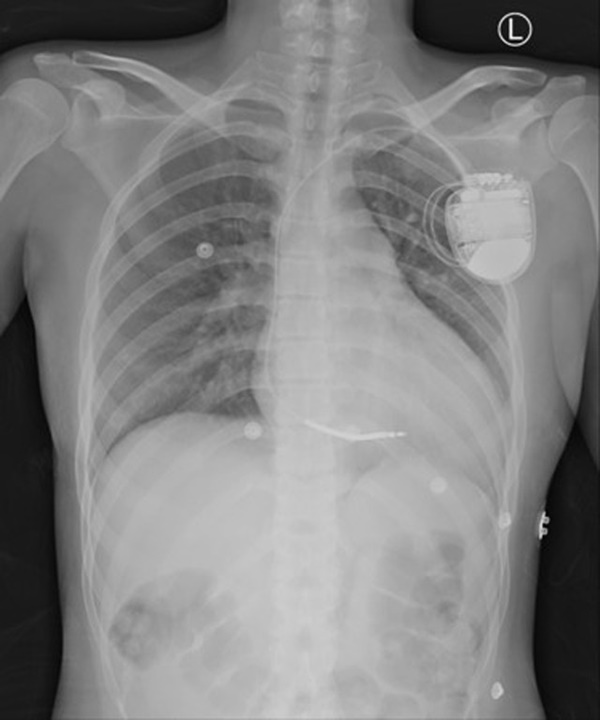

Bác sĩ Lý Dịch Đạt tiến hành cấy ghép máy khử rung tim (ICD) cho bệnh nhân, đồng thời điều chỉnh liều lượng sử dụng thuốc đã kê đơn ban đầu. Tiểu Vân đã xuất viện về nhà và không còn xảy ra tình trạng ngất xỉu.